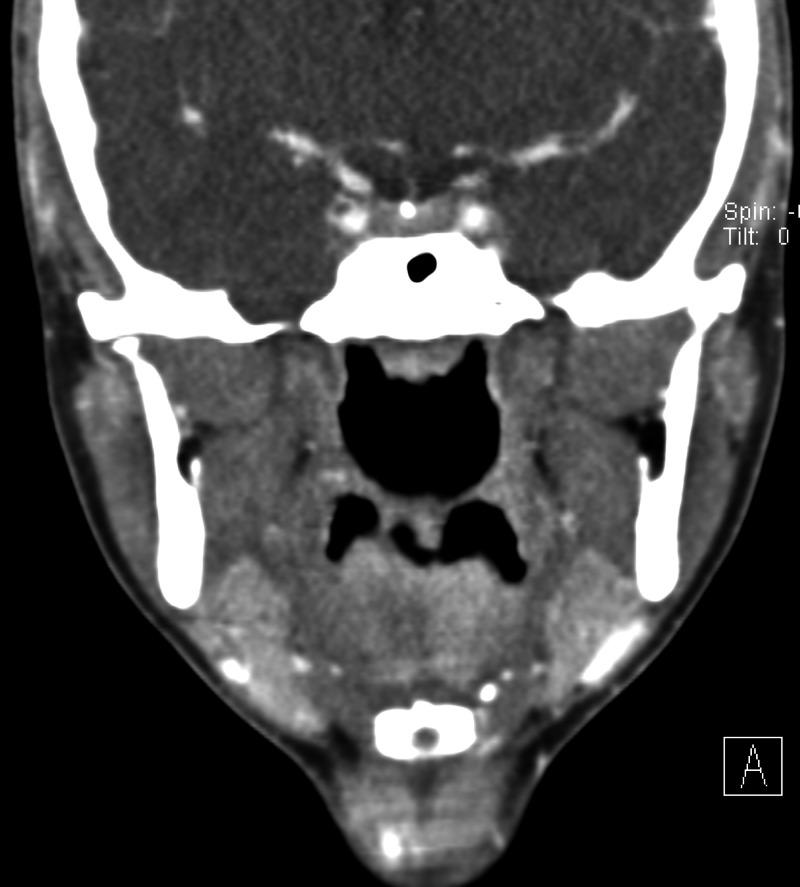

Idiopathic mandibular condylar resorption is a rare condition in which the mandibular condyle of the temporomandibular joint (TMJ) becomes resorbed and thus reduces in size and volume. This leads to TMJ dysfunction that commonly requires surgical correction; however, more conservative interventions can also be utilized. We present a case of idiopathic mandibular condyle resorption in a 17-year-old female presenting with TMJ pain and clicking with mastication. A definitive diagnosis of this condition ultimately requires imaging studies, a reliable option being magnetic resonance imaging (MRI), which will reveal erosion of the mandibular condylar process (often bilaterally) with diminished mass and volume leading to the known sequelae of symptoms.

特发性下颌髁突吸收是一种罕见的病症,其中颞下颌关节(TMJ)的下颌髁突会被吸收,从而尺寸和体积减小。这会导致颞下颌关节功能障碍,通常需要手术矫正;然而,也可以采用更保守的干预措施。我们报告一例17岁女性特发性下颌髁突吸收病例,该患者表现为颞下颌关节疼痛以及咀嚼时弹响。对这种病症的明确诊断最终需要影像学检查,可靠的选择是磁共振成像(MRI),它将显示下颌髁突的侵蚀(通常为双侧),伴有质量和体积减小,进而导致已知的一系列症状。